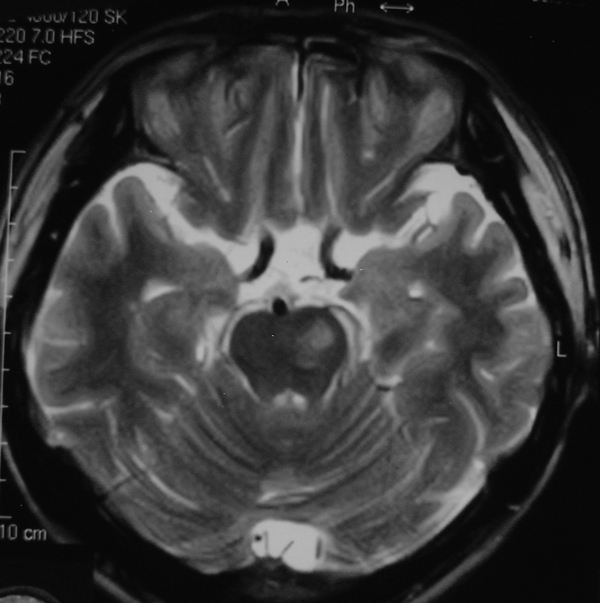

男 49岁 脑干腔隙梗塞5年。

这患者脑干(脑桥)腔隙脑梗塞是肯定的 有20002年资料 明天上传全部资料(当时工作忙 来不及)

1 单纯此图像定脑干梗塞依据不足. 2 可薄扫或核磁检查.

诊断依据不足,建议磁共振检查,

做磁共振吧!

脑干中脑区的梗塞还是能诊断的,建议薄扫一下。或者mri检查

脑干梗塞在ct上是斑点状低密度,一般只能在桥脑或中脑才能显示,延髓是很难发现(伪影多)。mr上脑干梗塞应该是长t1长t2的斑点状表现。弥散能够发现早期梗塞灶,表现高信号。

而小脑脚有三部分:①小脑下脚(绳状体)由脊髓小脑束组成, ②小脑中脚(脑桥臂)由脑桥小脑束组成, ③小脚上脚(结合臂)由出小脑纤维组成。小脑脚是正常神经纤维束构成,所以ct上密度是正常的(因为ct尚不能分辨脑干的细小神经纤维束);mr上是与正常白质一样的信号,而不是长t1长t2信号。

mri的优势